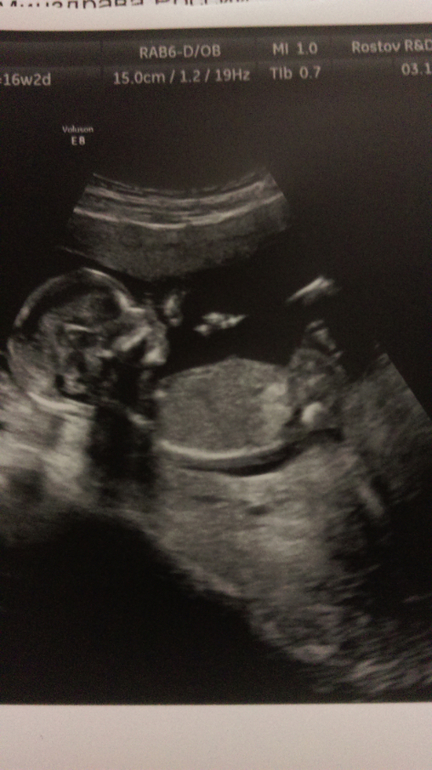

В четверг была на УЗИ. Мои внутренние ощущения оправдались - это девочка!!! Надеюсь, что будет без сюрпризов )))

По УЗИ все в норме, вес 150г уже примерно.

Сделали несколько фотографий, я их очень ждала, чтобы дочке их показать и рассказать, но до сих пор этого не сделала... Прошлые страхи дают о себе знать...

Следующее контрольное УЗИ аж 5 декабря! Очень жду его!!! Все будет хорошо, я верю!!!